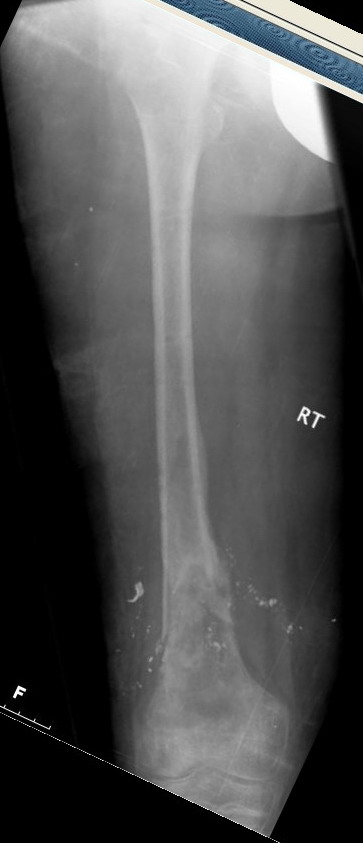

Выше приведены рентгенограммы 13-летнего подростка, страдающего от огнестрельного многооскольчатого перелома дистальной трети бедра. AO наружный фиксатор наложенный в день травмы не дал приемлемой редукции. Через три недели после перелома аппарат Илизарова был наложен без попытки одномоментной репозиции на операционном столе.

There are X-Rays of a thirteen year old boy with a comminuted distal femur fracture secondary to a gunshot wound, initially treated with an AO external fixator. The alignment was unacceptable and an Ilizarov external fixator was applied three weeks after the injury. No attempt of definitive reduction was made during the surgery.

Гексаподная приставки наложена на 10 дней и приемлемая редукция была получена.

The Hexapod set was applied for ten days and acceptable reduction was received.

По окончанию редукции Гексаподный сет был снят и дальнейшее ведение больного проходило в стандартном режиме аппарата Илизарова. Хороший анатомо-функциональный результат был получен.

When reduction was finished, the Hexapod set was removed and further management has been continued by standard Ilizarov regime. Good anatomic and functional results were achieved.